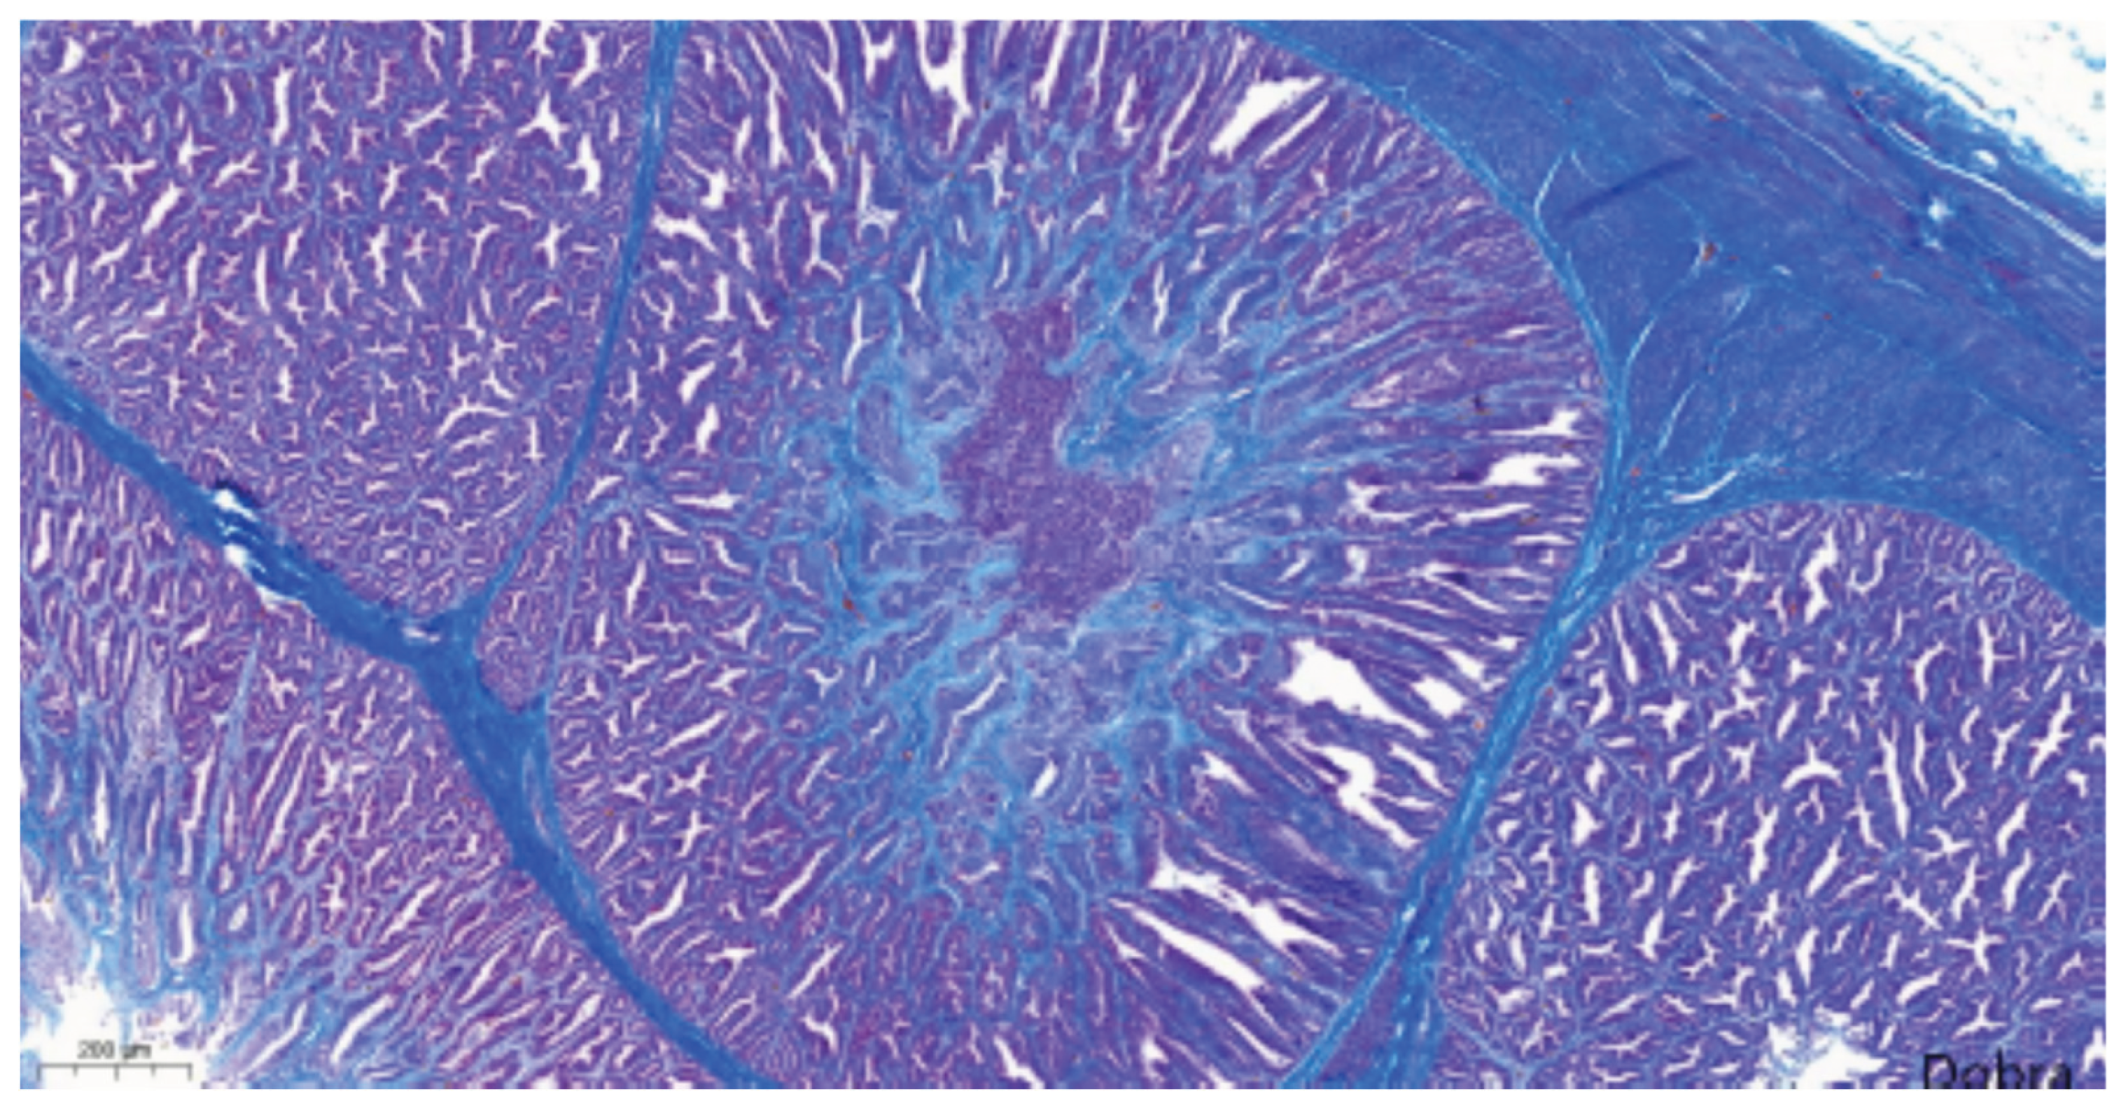

Most proventricular glands exhibited lesions consistent with chronic TVP, including ductal epithelial hyperplasia, epithelial metaplasia, and mild multifocal, lymphocytic infiltration (Figure 10). Masson's trichrome staining confirmed interstitial fibrosis (Figure 11). In addition, acute lesions characterized by glandular epithelial degeneration and necrosis with diffuse lymphocytic infiltration were present in some areas (Figure 12).

Figure 11. Meat-type PS chicken, proventriculus: interstitial fibrosis (proliferated connective tissue fibres appear in blue), Masson's trichrome staining, scale bar = 200 µm.

Histopathological evaluation of proventricular tissues further supported a diagnosis of TVP [2,3,4,5,6,7,8,9,11]. The lesions observed in this study, including glandular epithelial degeneration and necrosis, mononuclear infiltration, epithelial hyperplasia, metaplasia, and varying degrees of interstitial fibrosis, align closely with the classical microscopic features described in experimental infections with TVP-affected proventricular homogenates [2,4,10,28] and CPNV [29]. The concurrent presence of both acute and chronic lesions suggests that the infection in the flock may have persisted or occurred in multiple waves.